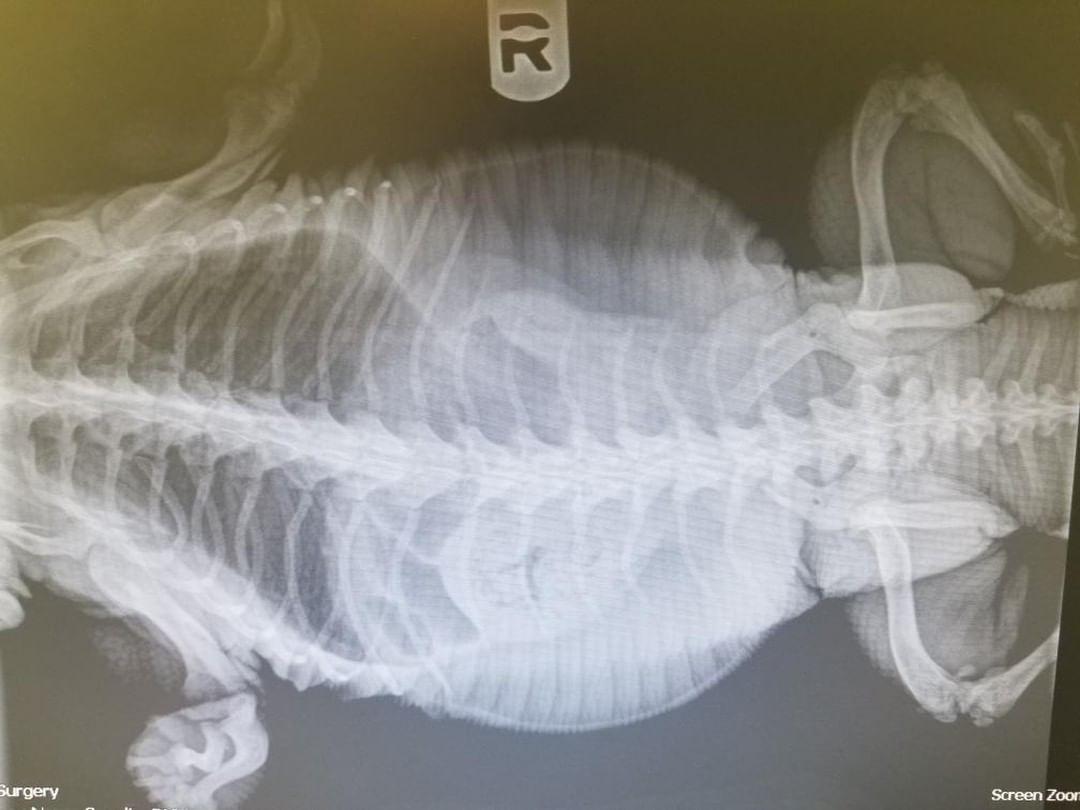

- Black and White Tegus